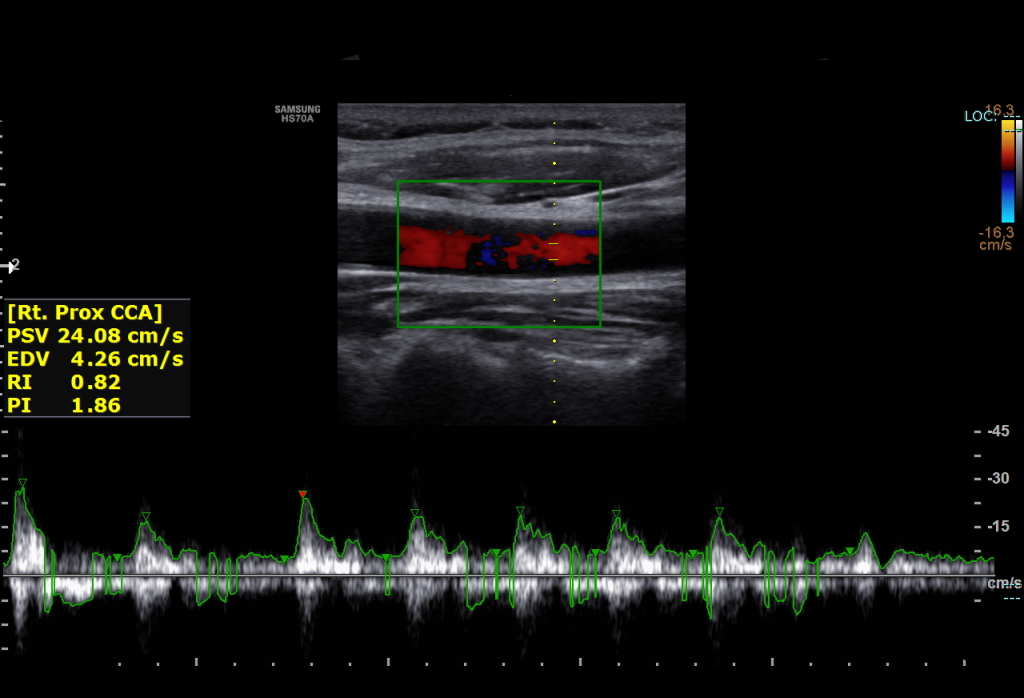

온목동맥의 상태와 건강은 도플러 초음파, CT 혈관조영술 또는 위상 대비 자기 공명 영상(PC-MRI)을 사용하여 평가한다.

일반적으로 온목동맥의 혈류 속도는 최고 수축기 속도(PSV)와 최종 이완기 속도(EDV)로 측정한다. 20~29세의 정상적인 남성을 대상으로 한 연구에서 평균 PSV는 115cm/sec, EDV는 32cm/sec였다. 80세 이상의 남성의 경우 평균 PSV는 88cm/sec, EDV는 17cm/sec였다.[7]